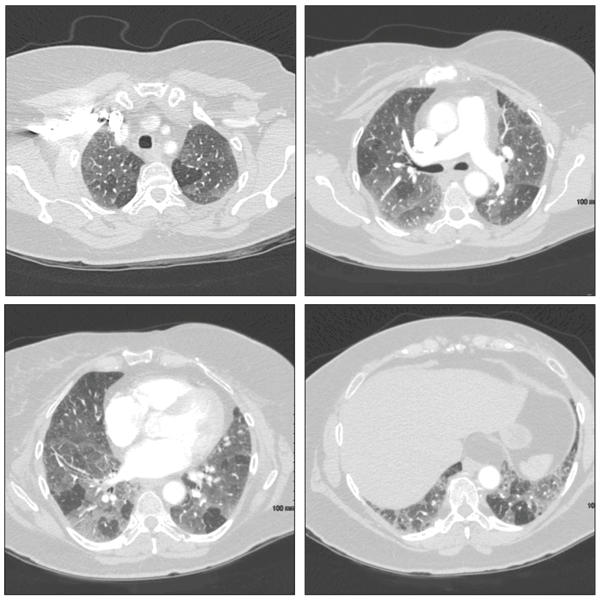

Drug-induced hypersensitivity pneumonitis is a clinically distinct pulmonary syndrome characterized by a complex immunological reaction.12 Patients may present with acute, subacute, or chronic symptoms of fevers, chills, malaise, and dyspnea. Pulmonary function tests demonstrate a reduced FVC and carbon monoxide–diffusing capacity (DLCO). High-resolution CT (HRCT) of the chest may reveal bilateral upper lobe–predominant ground-glass opacities, poorly defined centrilobular nodules, and air trapping on expiratory scans (Figure 1).

Figure 1 – These CT scans are from a patient with a subacute hypersensitivity reaction to nitrofurantoin. Findings include bilateral patchy areas of ground-glass opacity and areas of air trapping.

In chronic cases, radiographic and HRCT features may progress to fibrotic changes, including honeycombing and traction bronchiectasis (Figure 2).13 Lung biopsy specimens demonstrate loosely formed granulomas near the terminal bronchioles and lymphocytic and plasma cell infiltration of the alveolar walls (Figure 3). Pathology may demonstrate a nonspecific or usual interstitial pneumonitis pattern.13

Figure 2 – Examination of the lung parenchyma demonstrates diffuse ground-glass opacities and fibrotic changes, including areas of reticulation and honeycombing, which are worse at the periphery and the lung bases. Scattered areas of dilated airways are consistent with traction bronchiectasis.